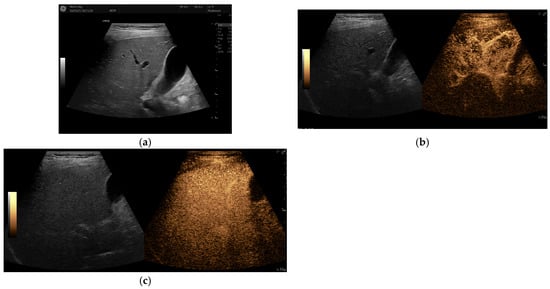

In addition to standardized lateral cephalometric radiographs, comprehensive assessment using dental cone-beam computed tomography (CBCT) and CT has become commonplace in the diagnosis and treatment of jaw deformities. Simulation based on cephalometr...